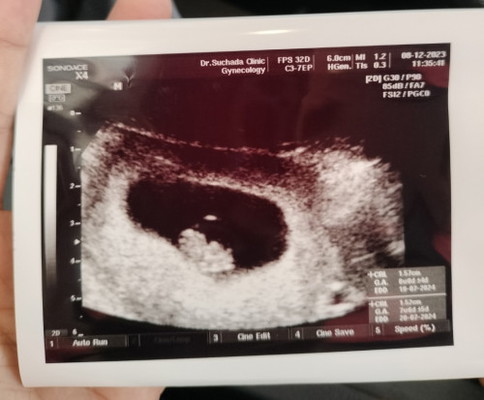

จากที่ก่อนหน้านี้น้องได้หลุดไปเมื่อกันยาที่ผ่านมา และน้องก็กลับมาใหม่พย. ตอนนี้ไปเจอคุณหมอมาแล้วนะคะ อายุครรภ์8Wแล้ว หมอบอกน้ำหนักตามเกณฑ์ หัวใจเต้นปกติ🥰